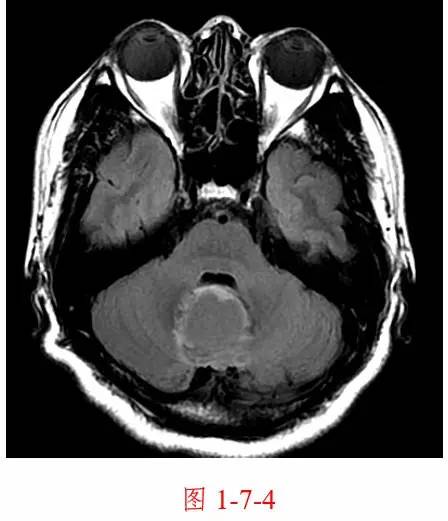

图 1-7-4 颅脑轴位 flair 图, 脑脊液信号被抑制,肿瘤周围水肿仍为高